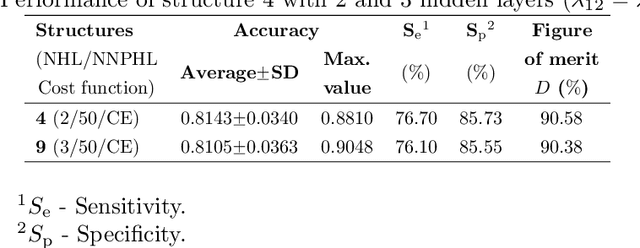

A Pathology-Based Machine Learning Method to Assist in Epithelial Dysplasia Diagnosis

Abstract:The Epithelial Dysplasia (ED) is a tissue alteration commonly present in lesions preceding oral cancer, being its presence one of the most important factors in the progression toward carcinoma. This study proposes a method to design a low computational cost classification system to support the detection of dysplastic epithelia, contributing to reduce the variability of pathologist assessments. We employ a multilayer artificial neural network (MLP-ANN) and defining the regions of the epithelium to be assessed based on the knowledge of the pathologist. The performance of the proposed solution was statistically evaluated. The implemented MLP-ANN presented an average accuracy of 87%, with a variability much inferior to that obtained from three trained evaluators. Moreover, the proposed solution led to results which are very close to those obtained using a convolutional neural network (CNN) implemented by transfer learning, with 100 times less computational complexity. In conclusion, our results show that a simple neural network structure can lead to a performance equivalent to that of much more complex structures, which are routinely used in the literature.